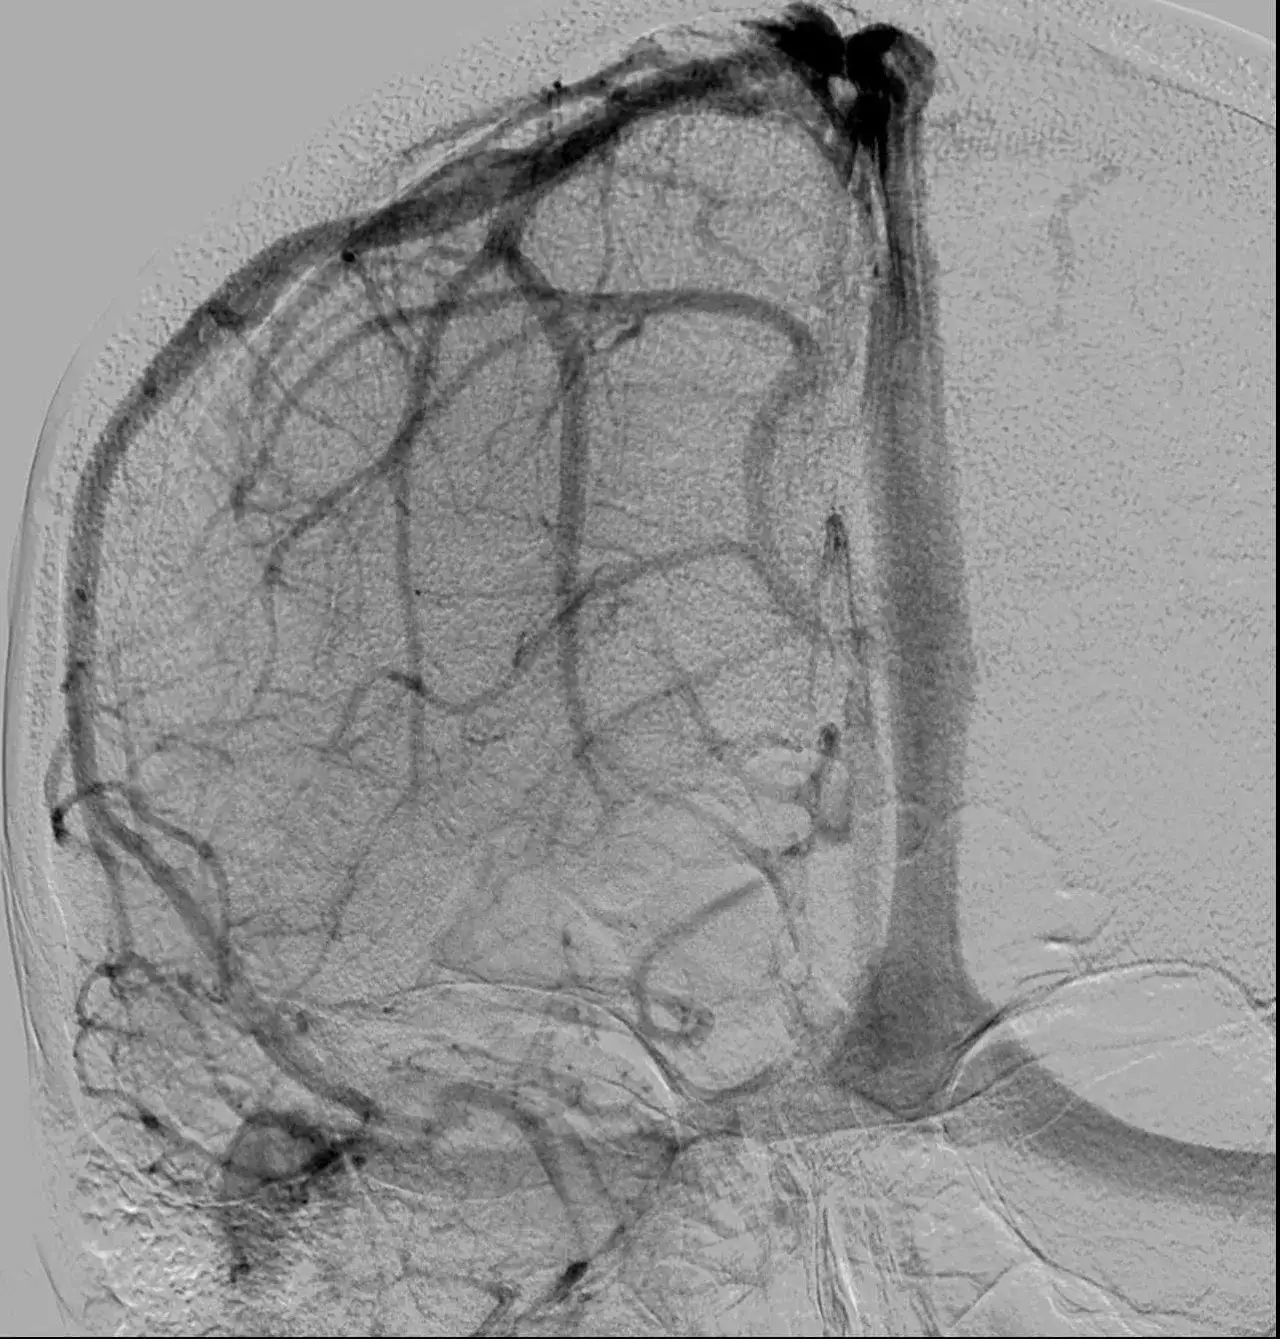

Diagnostyka problemów związanych z zatoką strzałkową górną jest kluczowa dla skutecznego leczenia. Wśród najczęściej stosowanych metod diagnostycznych znajduje się rezonans magnetyczny (MRI), który pozwala na dokładne obrazowanie zatok oraz otaczających struktur mózgowych. Inne techniki, takie jak tomografia komputerowa (CT), również mogą być użyteczne w ocenie stanu zatoki oraz identyfikacji ewentualnych patologii, takich jak zakrzepica czy zapalenie.

W przypadku wykrycia problemów, takich jak zakrzepica zatoki strzałkowej górnej, leczenie zazwyczaj obejmuje stosowanie leków przeciwzakrzepowych, które pomagają w rozpuszczeniu skrzepów i przywróceniu prawidłowego przepływu krwi. W bardziej zaawansowanych przypadkach może być konieczna interwencja chirurgiczna, aby usunąć przeszkody lub zredukować ciśnienie w obrębie mózgu. Właściwe leczenie jest kluczowe, aby zapobiec poważnym komplikacjom zdrowotnym.

- Rezonans magnetyczny (MRI) - dokładne obrazowanie zatok i struktur mózgowych.

- Tomografia komputerowa (CT) - ocena stanu zatoki oraz identyfikacja patologii.